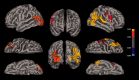

Noninvasive brain imaging methods provide useful information on cerebral involution and degenerative processes. Here we assessed cortical degeneration in 20 nondemented patients with Parkinson's disease (PD) and 20 healthy controls using three quantitative neuroanatomical approaches: voxel-based morphometry (VBM), cortical folding (BrainVisa), and cortical thickness (FreeSurfer). We examined the relationship between global and regional gray matter (GM) volumes, sulcal indices, and thickness measures derived from the previous methods as well as their association with cognitive performance, age, severity of motor symptoms, and disease stage. VBM analyses showed GM volume reductions in the left temporal gyrus in patients compared with controls. Cortical folding measures revealed significant decreases in the left frontal and right collateral sulci in patients. Finally, analysis of cortical thickness showed widespread cortical thinning in right lateral occipital, parietal and left temporal, frontal, and premotor regions. We found that, in patients, all global anatomical measures correlated with age, while GM volume and cortical thickness significantly correlated with disease stage. In controls, a significant association was found between global GM volume and cortical folding with age. Overall these results suggest that the three different methods provide complementary and related information on neurodegenerative changes occurring in PD, however, surface-based measures of cortical folding and especially cortical thickness seem to be more sensitive than VBM to identify regional GM changes associated to PD.